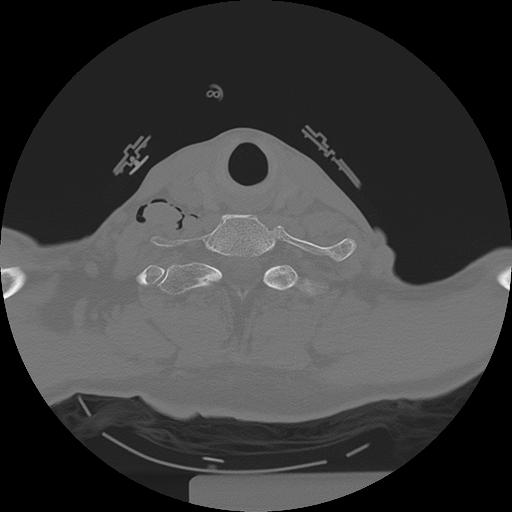

11 HUESO,,Axial,2.0,HUESO,,